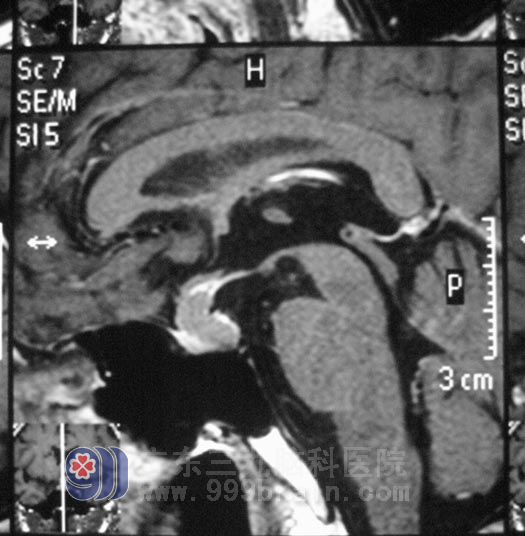

术前磁共振片